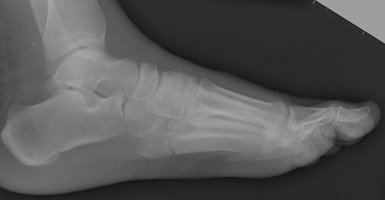

A Jones fracture is a fracture of the fifth metatarsal of the foot. The fifth metatarsal is at the base of the small toe, and the proximal end, where the Jones fracture occurs, is in the midportion of the foot. Patients who sustain a Jones fracture have pain over this middle/outside area of their foot, swelling, and difficulty walking.

a jones fracture